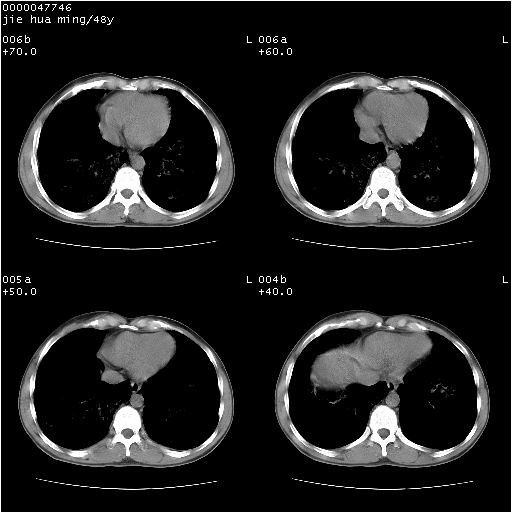

以下是引用dr.yang在2008-5-1 6:25:00的发言:[br]两肺广泛毛玻璃样的片状影,密度不均,边缘欠清,呈碎石路样改变,[br]考虑,1双肺间质性肺炎,2肺泡蛋白沉积症3支气管肺泡癌[br]

以下是引用hhcckk在2008-5-1 8:06:00的发言:[br]支持肺泡蛋白沉积症[br]依据:[br]1、病灶边缘清楚----地图征[br]2、病灶内部小叶间隔或小叶内间隔增厚所形成的网格状影----碎石路样表现[br]3、抗炎治疗无效(炎症抗炎治疗有效)[br]4、纵隔内未见肿大淋巴结(肺泡细胞癌时常有)[br][br]附肺泡蛋白沉积症资料[br][br]肺泡蛋白沉积症(pulmonary alveolar proteinosis)是一种原因不明的以肺泡腔内大量含脂糖蛋白样物质沉积为特征的疾病。[br]病理改变:(1)肺泡和细支气管腔内充满大量含脂糖蛋白样的粘稠物质,该物质为颗粒状或絮状的糖原pas染色阳性的磷脂蛋白。(2)肺泡壁及其间隔无异常改变。胸膜和淋巴结不受累及。(3)晚期可出现弥漫性肺间质纤维化。[br]临床表现:(1)好发年龄30~50岁,男性多于女性,偶见于儿童;(2)主要症状为呼吸困难、咳嗽、低热、消瘦、低氧血症和杵状指等。1/3的患者无症状。(3)实验室检查:痰液或肺泡灌洗液中可找到pas染色阳性颗粒物质。[br]hrct表现:肺泡蛋白沉积症具有特征性改变,即“碎石路样”表现(crazy-paving appearance,cpa)。主要包括(1)斑片状磨玻璃影:指肺野密度朦胧增加,内可见肺血管纹理影,系肺泡腔内充满低密度的磷脂蛋白物质所致。(2)其内部小叶间隔或小叶内间隔增厚所形成的网格状影,为小叶间隔水肿、肺泡壁内淋巴细胞和巨噬细胞浸润以及小叶内淋巴管扩张的缘故。(3)病灶边缘清楚,呈地图样分布于肺野外围或肺门及中央区。[br]

以下是引用zsl6918在2008-5-1 7:35:00的发言:[br]双肺磨玻璃样病变,可见铺碎路石征,病变区与正常区交错。边界清晰。符合肺泡蛋白质沉着征,高分辨扫描会更清楚漂亮。建议临床肺泡灌洗。

以下是引用yangyudong333在2008-5-1 5:36:00的发言:[br][br] 两肺广泛毛玻璃样的片状影,密度不均,边缘欠清,呈碎石路样改变,[br]考虑,1双肺间质性肺炎,2肺泡蛋白沉积症[br]